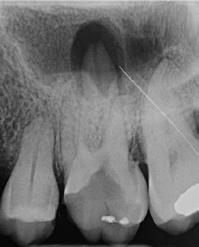

1. ábra: A 15-ös foggyökér meziális felszíne mellett látható radiolucens elváltozás, illetve a felvételen látható a korábban behelyezett gyökértömés, a parapulpális csap segítségével elhorgonyzott csonkfelépítés és a fogat borító cirkonkorona. –2. ábra: A saggitalis irányú CBCT-metszeten jól megfigyelhető az állcsontgerincet elérő radiolucens elváltozás. – 3. ábra: Az axiális irányú CBCT-metszeten egyértelműen látható a kezeletlen palatinális gyökércsatorna, valamint a radiolucens elváltozás mezio-disztális kiterjedése is jól megítélhető. – 4. ábra: A palatinális gyökércsatorna szelektív endodonciai kezelése során először gyógyszeres zárás került behelyezésre. – 5. ábra: A gyógyszeres zárás során alkalmazott kalcium-hidroxid alapú paszta a szulkuszon keresztül a szájüregbe extrudálódott. – 6. ábra: A gyökértömő anyag a középső és apikális gyökéri harmad határán lévő laterális csatornán keresztül a periapikális térbe extrudálódott. 7. ábra: A kezelések befejezését követően 4 évvel készült röntgenfelvételen jól látható a csontállomány gyógyulása és a fiziológiás gyökérhártyarés újbóli kialakulása. –8. ábra: A peroperatív CBCT-felvétel alapján készített koronális irányú metszeten jól látható a gyökércsúcs körül lévő periapikális felritkulás. – 9. ábra: A kezelések befejezése után 4 évvel készített CBCT-felvételen a gyulladásos lézió teljes megszűnése észlelhető.

A CBCT-készülékek endodonciai alkalmazásának talán az az egyik legnagyobb előnye, hogy így olyan anatómiai struktúrák is láthatóvá válnak, amelyeket egyébként nem tudnánk detektálni panoráma, cephalo, vagy periapicalis felvételek segítségével. Mivel a CBCT-felvételek kiértékelése számítógép segítségével történik, így a felvételek vizsgálata során lehetőségünk van az adott területet több nézőpontból és több síkban is megvizsgálni. 2015 októberében egy korábban a rendelőnkben kezelt 55 éves férfi páciens azzal a céllal kereste fel ismét a rendelőnket, hogy másodvéleményt kérjen egy jobb felső kvadránsban található fogával kapcsolatban. Egy másik rendelőben történő vizsgálat során a panaszos fog törését vélelmezték és a fog eltávolítását javasolták, illetve arról is beszámolt, hogy az elmúlt hét során ezen a területen egy puha duzzanat is kialakult. A klinikai vizsgálat során a jobb felső első és második kisőrlő között (14–15) egy fluktuáló duzzanatot észleltünk az áthajlásban. Az 15-ös fog mesialis oldalán 12 mm mély tasakot szondáztunk. A páciens által hozott periapicalis felvételen a 15-ös fog gyökércsúcsának mesialis részén egy nagy kiterjedésű radiolucens elváltozás volt észlelhető (1. ábra). A saggitális síkban vizsgált CBCT-felvételen (Carestream CS 9000, Carestream Dental) a lézió valódi kiterjedése is láthatóvá vált (2. ábra). A megelőző endodonciai kezelések során csupán a bukkális csatorna került detektálásra és gyökértöméssel való ellátásra. Az axiális irányú CBCT-szeleteken egyértelműen látható volt az ellátatlan palatinális gyökércsatorna (3. ábra)

Először kalcium-hidroxid alapú ideglenes gyógyszeres zárás került a palatinális csatornába (UltraCal XS, Ultradent Products; 4–5. ábra), amelyet 6 hét után a végleges gyökértömés elkészítése előtt eltávolítottunk. A gyökértömés elkészítése során meleg vertikális kondenzációs technikát alkalmaztunk. Radiológiai felvételen megfigyelhető volt, hogy a gyökértömő anyag egy laterális csatornán keresztül kis mennyiségben a periapicalis térbe extrudálódott (6. ábra). A 4 évvel később készített kontrollfelvételeken a lézió gyógyulása volt megfigyelhető (7–9. ábra). A vizsgálati eredmények és a kezelés kimenetele egyértelműen igazolta, hogy nem gyökérfraktúrával álltunk szemben, tehát a kezdeti diagnózis tévesnek bizonyult. Ez is azt erősíti, hogy korlátozott mennyiségben rendelkezésre álló adatok alapján nem lehet pontos diagnózist felállítani. Manapság szinte elengedhetetlen a CBCT-felvételek endodonciai beavatkozások során történő használata, feltéve, ha ezek elkészítése során az ALARA elv (as low as reasonably achievable) betartásra kerül.